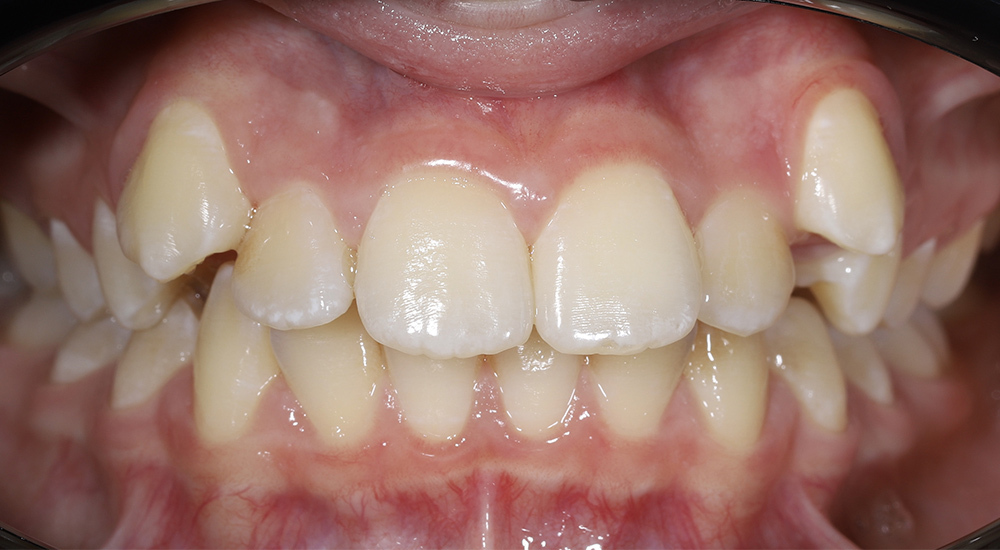

Коррекция прикуса и выравнивание зубных рядов у подростка несъёмной ортодонтической техникой